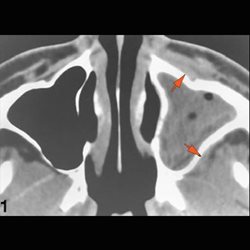

The orbit is susceptible to contiguous spread of infection from the sinuses.